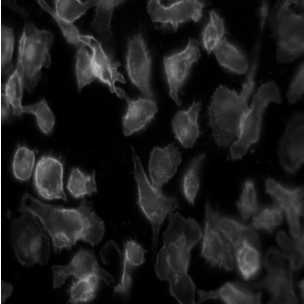

Deep-learning models have been successful in biomedical image segmentation. To generalize for real-world deployment, test-time augmentation (TTA) methods are often used to transform the test image into different versions that are hopefully closer to the training domain. Unfortunately, due to the vast diversity of instance scale and image styles, many augmented test images produce undesirable results, thus lowering the overall performance. This work proposes a new TTA framework, S$^3$-TTA, which selects the suitable image scale and style for each test image based on a transformation consistency metric. In addition, S$^3$-TTA constructs an end-to-end augmentation-segmentation joint-training pipeline to ensure a task-oriented augmentation. On public benchmarks for cell and lung segmentation, S$^3$-TTA demonstrates improvements over the prior art by 3.4% and 1.3%, respectively, by simply augmenting the input data in testing phase.